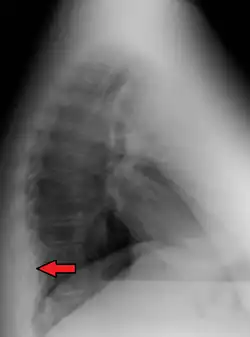

Mediastinal lipomatosis